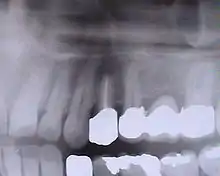

Contrôle de la cicatrisation à une semaine de l'intervention